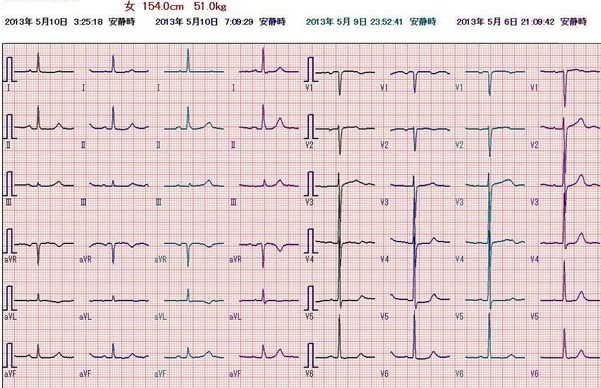

身体所見にその他、特記すべき異常所見はありません。その時にとられた心電図です。

これまで全く自覚症状のない人に左胸部痛が出現しています。吸気時に増強するという記載があり、非定型的ではありますが、まず急性冠症候群を考えます。冷汗と嘔吐という全身症状を伴っており、手術後の痛みや不安感だけでは説明できません。鑑別診断としては急性肺血栓塞栓症ですが、SpO2が正常であることから否定的です。緊急で施行した心エコー検査でも右室負荷の所見はみられませんでした。 心電図の所見は、Ⅰ、aVL、V4-6でT波の逆転、ないし平低化を認めます。術前にとられた心電図を示します。術前の心電図と比較すると、問題の心電図異常は新しく起きた変化であることが分かります。この所見からは、左室高位側壁、左室前壁から側壁にかけて心筋虚血がおこっている可能性があります。

術前心電図

患者さんの症状は急速に改善、処置が終了し病室に帰室されました。 心電図の経過をみると、

変化は明らかですが、その後、心筋逸脱酵素の上昇もなく心筋梗塞は回避できたと考えています。

心電図の経過